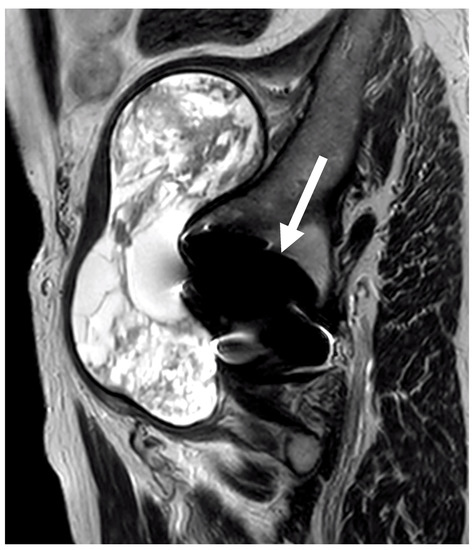

3.6. Imaging Data

- Sabah, S.A.; Mitchell, A.W.; Henckel, J.; Sandison, A.; Skinner, J.A.; Hart, A.J. Magnetic resonance imaging findings in painful metal-on-metal hips: A prospective study. J. Arthroplast. 2011, 26, 71–76.e2. [Google Scholar] [CrossRef]

- Hjorth, M.H.; Mechlenburg, I.; Soballe, K.; Romer, L.; Jakobsen, S.S.; Stilling, M. The anatomical location of cystic pseudotumors and muscle atrophy in metal-on-metal resurfacing hip arthroplasty is related to the surgical approach used for implantation. A subgroup analyses of a randomized controlled trial. Arch. Orthop. Trauma. Surg. 2023, 1–10. [Google Scholar] [CrossRef] [PubMed]

- Hauptfleisch, J.; Pandit, H.; Grammatopoulos, G.; Gill, H.S.; Murray, D.W.; Ostlere, S. A MRI classification of periprosthetic soft tissue masses (pseudotumours) associated with metal-on-metal resurfacing hip arthroplasty. Skelet. Radiol. 2012, 41, 149–155. [Google Scholar] [CrossRef]

| MARS/MRI | Muscle changes | 1 (3%) | 8 (26%) | 5 (17%) | 0.001 |

| Fluid accumulations | 2 (6%) | 4 (13%) | 4 (13%) | 0.001 | |

| Mass | 1 (3%) | 2 (6%) | 0 | 0.2 |